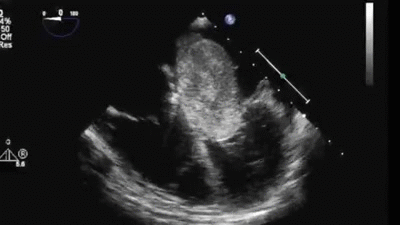

***心脏超声波

文章插图

首先看一看“门” , 也就是瓣膜 , 有没有坏掉 。

门是大是小?打得开吗?关得拢吗?

门上有没有乱七八糟的东西 , 比如赘生物?

然后看一看“墙壁” , 也就是心肌 , 有没有问题 。

墙壁厚不厚?薄不薄?有没有不均匀?有没有洞?

再看看墙壁组成的“房间” , 也就是心房和心室 , 有没有问题 。

房间会不会太大或者太小?

房间里有没有长奇怪的东西 , 比如血栓 , 或者肿瘤?

房子不会动 , 但我们的心脏是会活动 , 收缩和舒张的功能也要考察 。

心脏超声也能检查:收缩的顺序对不对?收缩的力道够不够?对称不对称?